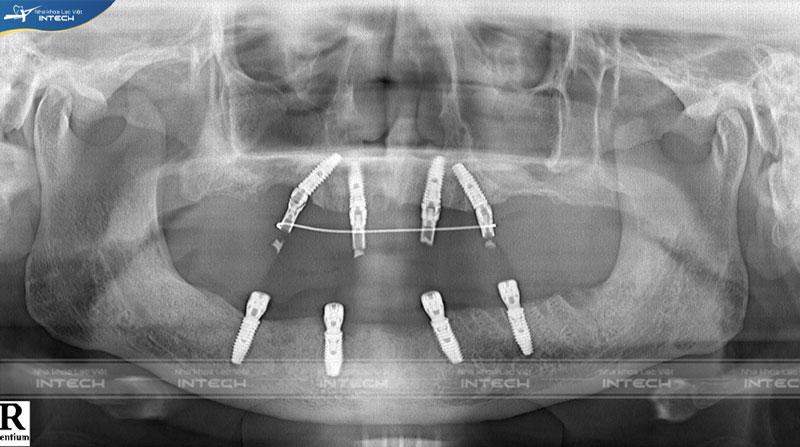

Dưới đây là hình ảnh phim chup X-quang của chú Toán sau khi cấy ghép Implant:

Ảnh chụp phim X-quang của chú Nguyễn Văn ToánẢnh chụp phim X-quang của chú Nguyễn Văn Toán